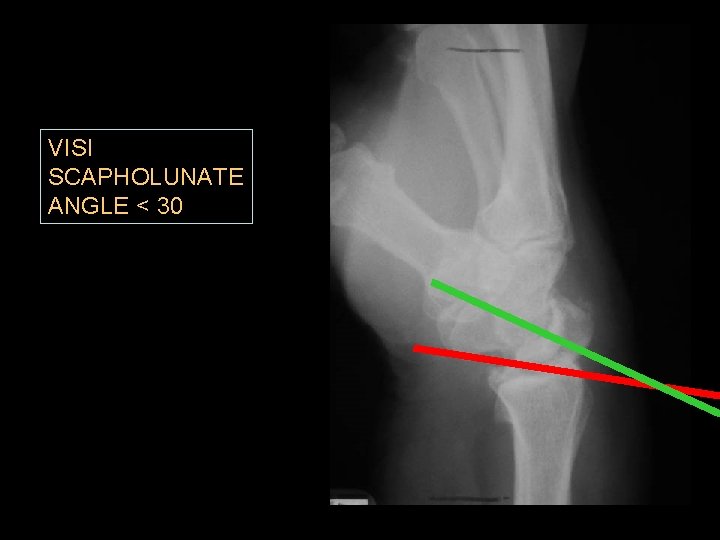

VISI SCAPHOLUNATE ANGLE < 30

VISI PATTERN LUNATE is the intercalated element

Static Midcarpal Instability • Static MCI results in flexion of the proximal carpal row and VISI